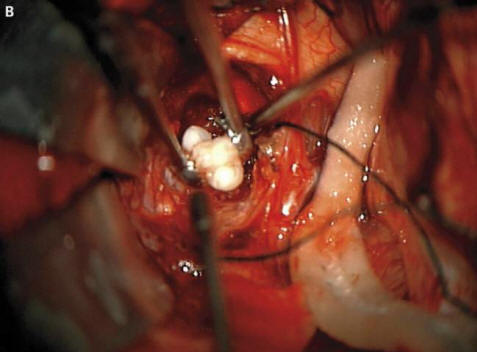

fénykép nyílt forrásból, ahogyan a sebészek elmondták a rémült szülőknek és onkológusok, ennek oka egy ritka veleszületett képződmény volt daganatok – craniopharyngiomas – írja a New England Journal of Medicine. Ez a daganat az esetek túlnyomó többségében jóindulatúak azonban egyre nagyobb lehet egy golyó – golf és okozza a szaglás, a hallás és látás romlását, és – szintén növeli az intrakraniális nyomást. A kutatók mindig gyanította, hogy ezek a daganatok már gyermekkorban megjelennek a fogakkal azonos sejtekből kialakult terhesség, mivel nagy kalciumfelhalmozódást észleltek, de egy valódi formájú fogat, amelyet ebben az esetben nem találnak elszámolni.

A sebészek sikeresen eltávolították a fényképet a nyílt forrásokból mondták, hogy a fiúnak jól van. Azonban egy fog, hogy nőtt fel az agyalapi mirigyében, de mégis megrontotta az agyat, megfelelő hormontermelés – a betegnek ezeket előbb be kell szednie az élet vége. Ez az eset jogosan büszke lehet a helyre az onkológusok legfurcsabb műveleteinek listája. Időközben iráni fiatalember, akinek kellett kezelje szőrös szemét. Szinte furcsa tumor jelent meg a szemében közvetlenül a születés után, de 19 éves korukra 2006 – ban jelentősen megnőtt méretét (legfeljebb 0,6 cm), és megakadályozta ezen felül a szemhéjak bezárását merev haj kezdett növekedni. Az orvosok eltávolították a tumort, és azt találták ez egy limbális dermoid – rendkívül ritka, általában jóindulatú oktatás. Az orvosok szerint ebben az esetben ha a fiatalember továbbra is gyógyszeresen húzza, akkor duzzanatot jelent nemcsak a hajat növeli, hanem izzadni is kezd: az idő múlásával daganatokban a megfelelő mirigyek gyakran megjelennek.